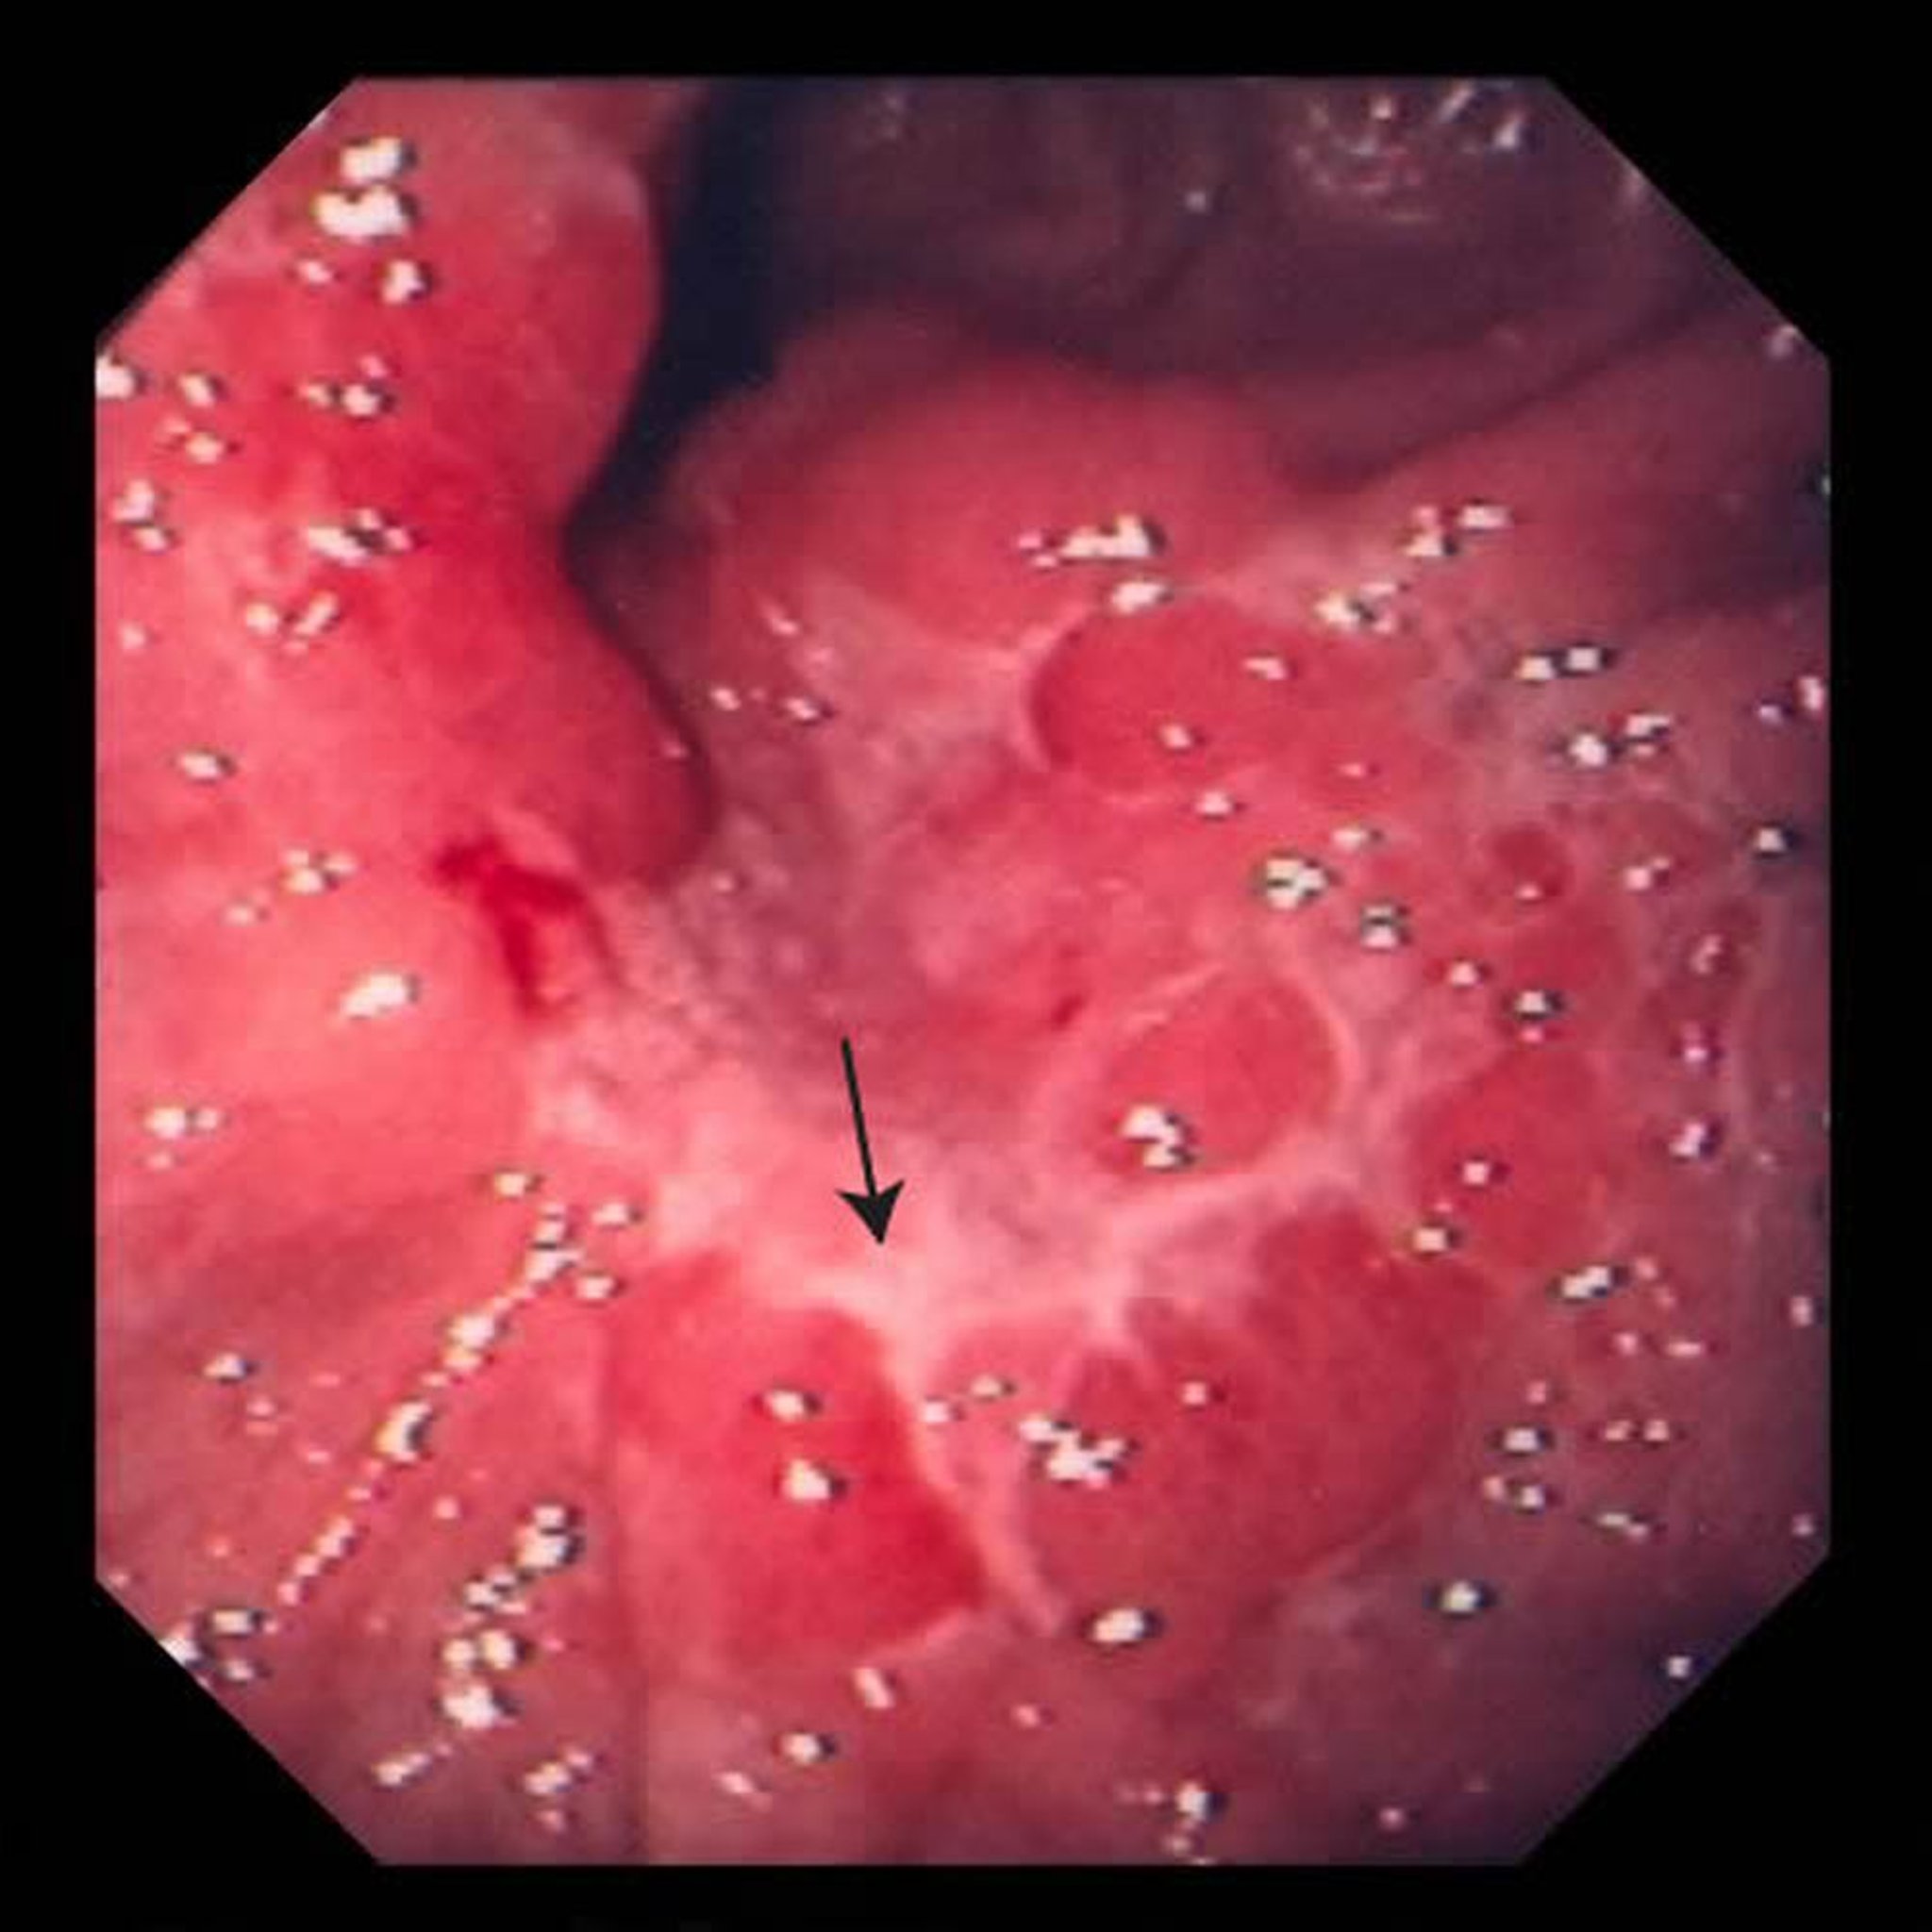

Esta imagen muestra una úlcera en el estómago (flecha). Después de una biopsia, los médicos determinaron que se trataba de un adenocarcinoma.

Imagen proporcionada por David M. Martin, MD.